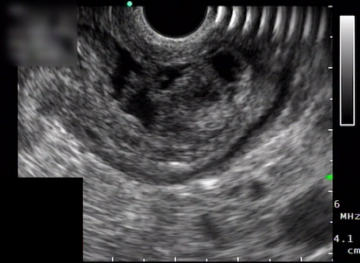

Präoperative Befunderhebung

Endosonographisch entspricht dieser Tumor einer echo-inhomogenen 26 × 12 mm großen Raumforderung innerhalb der Magenwand. -